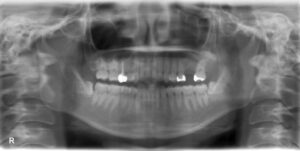

下顎大臼歯1本欠損症例

BEFORE AFTER 47歳男性/下顎1本欠損/インプラント埋込手術 【治療内容】 右下第二大臼歯の痛み、歯肉の腫れ…